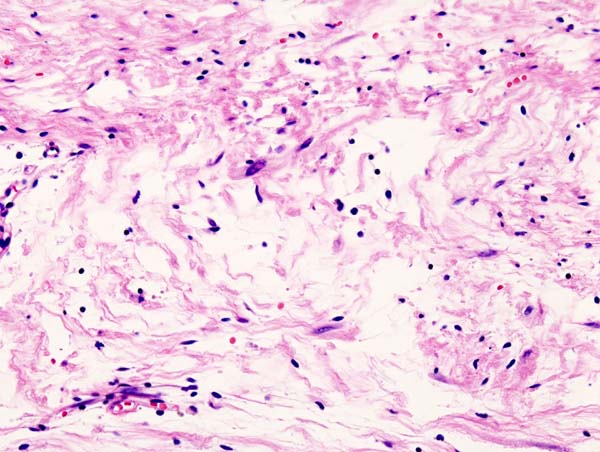

A pilocytic astrocytoma is a benign tumor of astrocytes.

Pilocytic astrocytomas are the most typical central nervous system tumor in children.

Pilocytic astrocytomas tends to develop in the cerebellum.

Radiology of pilocytic astrocytomas typically show a mural nodule and a cystic lesion are seen on imaging.

Histology of pilocytic astrocytomas shows eosinophilic granular aggregates and Rosenthal fibers (thick eosinophilic processes of the astrocytes).

The tumor cells of pilocytic astrocytomas are glial fibrillary acidic protein (GFAP) positive.